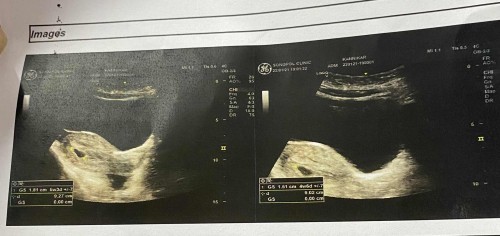

5 วีคเจอแค่ถุงตั้งครรภ์ แม่ๆเจอน้องกันตอนไหนบ้างคะ